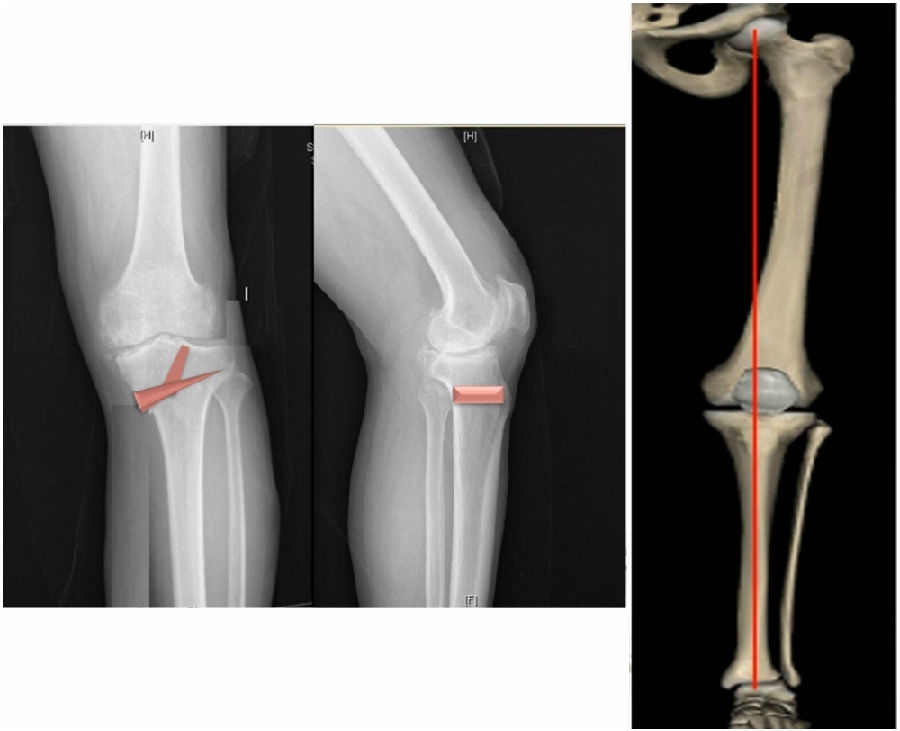

典型病例,男性,57岁,农民,左膝疼痛3年。

术前

术前影像资料

术前规划:

①关节内截骨,内外侧平台平行。

关节内截骨

②再次确定下肢力线。

确定力线

③关节外截骨。

关节外截骨

术中先打克氏针确定截骨方向,先做关节内截骨,截完后测量下肢力线,发现并没达到术前设计的Fujisawa点。

术中影像资料

随后用骨刀继续向前敲,做HTO内侧开放楔,截骨完成后内侧固定,并测量下肢力线,此时达到术前设计的要求。

该患者撑开较大,取了髂骨进行植骨。

最终力线

术后检查证实达到了术前预期的手术效果,关节线达到了平行,半脱位得到矫正,同时关节线和地面水平。病人行走达到了理想的效果。

术后X线

患者术后4个月截骨愈合,膝关节稳定维持得非常好。

术后4个月

术后9个月完全恢复功能状态。

术后9个月